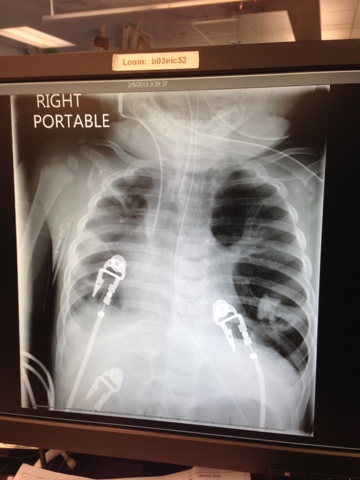

She had a good night! Yesterday they conducted a pressure support trial to allow her to breathe on her own to see how she could do. She handled it "like a boss" and lasted the whole hour. Today they did the test again twice and she did great. Her X-ray from today showed improvement as well. So- WOOOOHOOOO they just extubated and no more ventilator! So far she is holding her own and breathing on her own. Oh happy day!